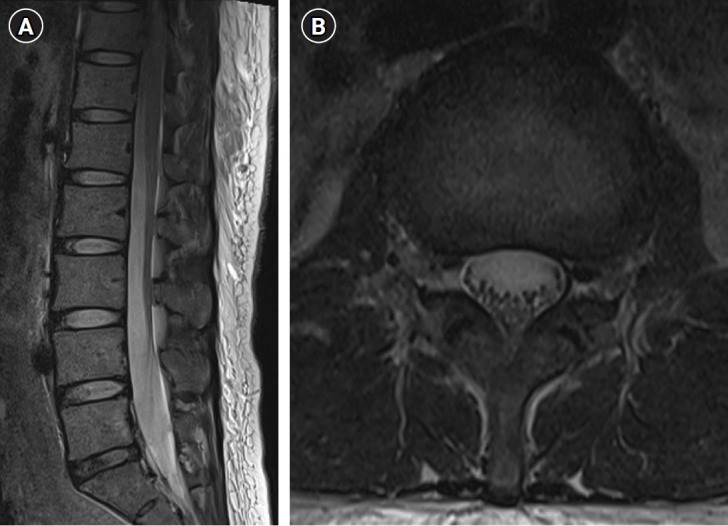

Cases: A 41-year-old pregnant woman was scheduled to undergo epidural anesthesia for cesarean section. After attempting epidural anesthesia, she experienced prolonged hypotension and recovery time, especially in the right extremity. Through magnetic resonance imaging we found subdural air bubbles compressing the right side of the cauda equina in the L3 region. Thus, we considered unintended subdural anesthesia and performed conservative management with close observation. Her symptoms completely resolved within 24 h.